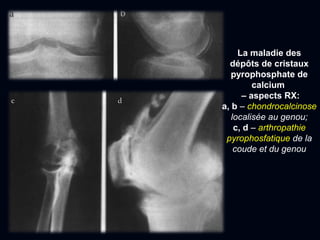

La maladie des

dépôts de cristaux

pyrophosphate de

calcium

– aspects RX:

a, b – chondrocalcinose

localisée au genou;

c, d – arthropathie

pyrophosfatique de la

coude et du genou